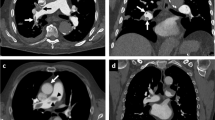

CPAP increased lung volume by 296 mL (SEM: 73; p < 0.001) and 243 mL (SEM: 52; p < 0.001), which corresponds to a mean relative increase of 8.0% (SEM: 2.2) and 6.3% (SEM: 1.3) at T0 and T1 time-points, respectively. The change in lung volume induced by CPAP showed a wide inter-patient variability (Fig. 1 and Table 2). For example, while some of the patients showed a large increase in lung volume at T0 (#16, #18 and #19; Fig. 2), two of the patients (#10 and #13) displayed a slight decrease, for which there is no obvious physiological explanation apart from anxiety (patient #13 was the one who did not tolerate CPAP well). Overall, the change in lung volume induced by CPAP at T0 was similar to T1 (interaction F = 0.31, p = 0.56). However, the intra-patient reproducibility was relatively low (Fig. 1).

In some patients (e.g. #16, #18 and #19), continuous positive airway pressure (CPAP) induced a large increase in lung volume. The noCPAPT0 midposition (MidP) CT, the CPAPT0 MidP CT and their fusion are displayed on the first, second and third rows, respectively. Lungs are delineated with a blue line